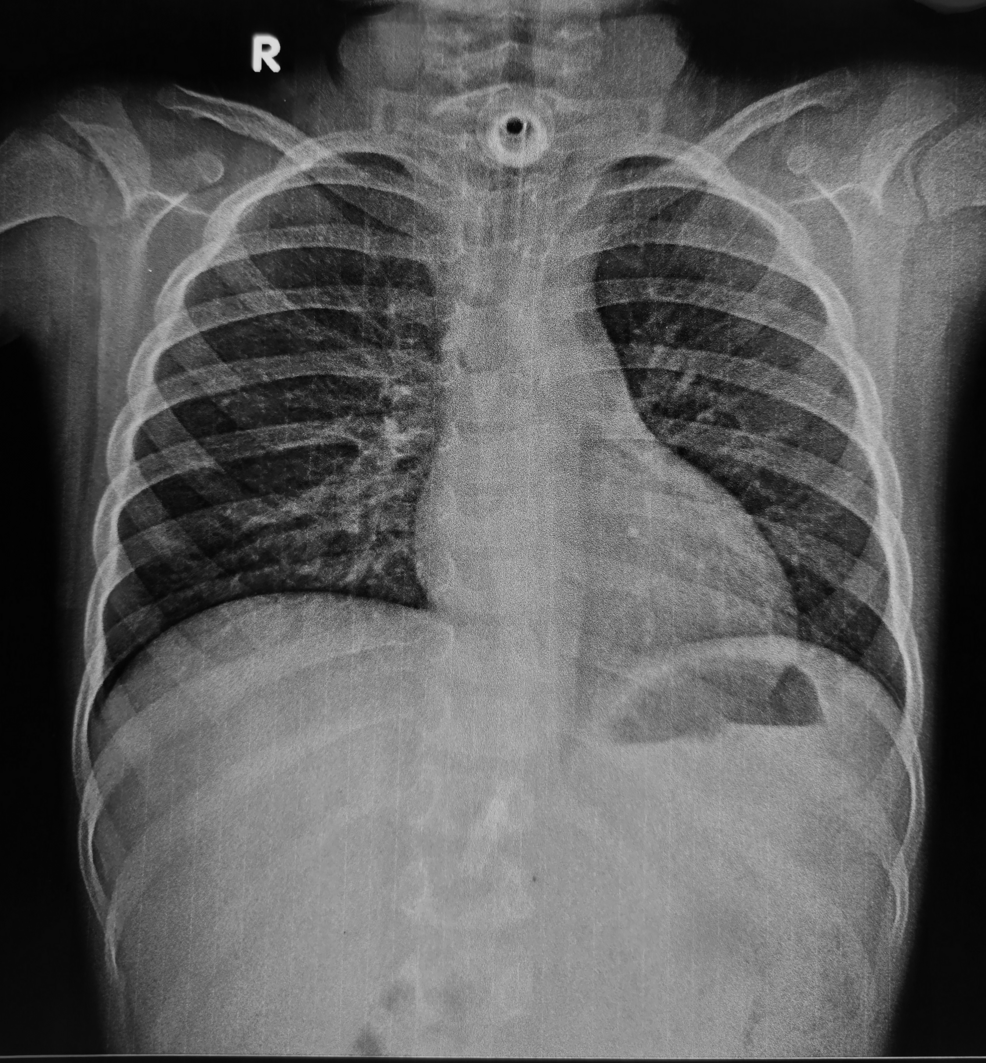

Regardless of specialization, technology will be a defining force. Artificial intelligence (AI) and machine learning (ML) are poised to revolutionize diagnostics, treatment planning, and drug discovery. For example, AI-powered image analysis is already assisting radiologists in detecting subtle anomalies in scans, improving accuracy and speed. Similarly, in cardiology, AI algorithms can predict heart failure risk with greater precision than traditional methods. This isn’t about replacing doctors, but augmenting their abilities.